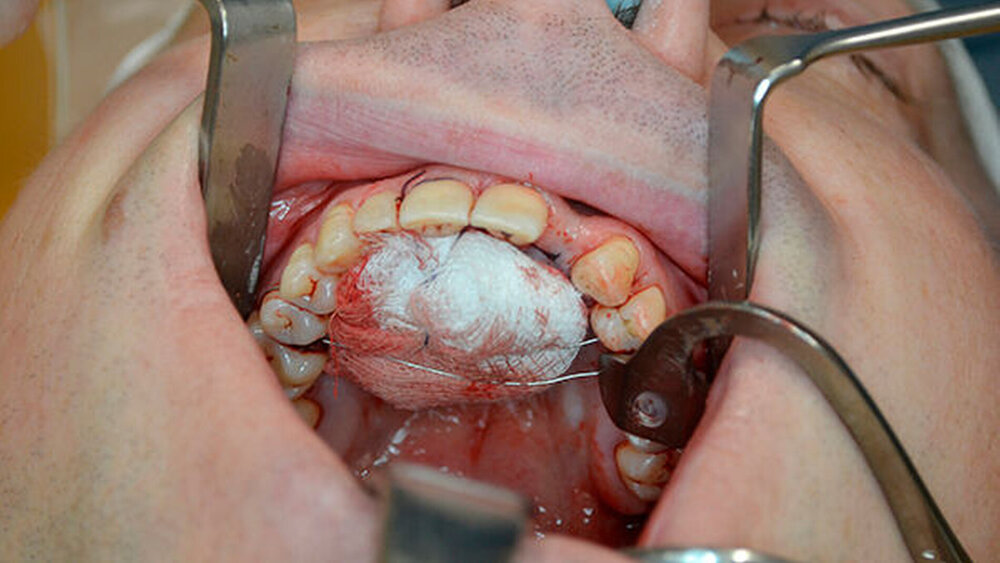

Die Zyste wurde in toto exstipiert und zur weiteren Diagnostik in die Pathologie abgegeben (Abbildung 5). Auf Grund eines Zystenvolumens von mehr als 2cm3in der DVT-Diagnostik wurde eine Knochenaugmentation mittels Beckenkammspongiosa durchgeführt. Nach enoralem Wundverschluss wurde ein Überknüpfverband mittels Iodoformvaselinestreifen angelegt und mittels Drahligaturen interdental fixiert (Abbildung 6).